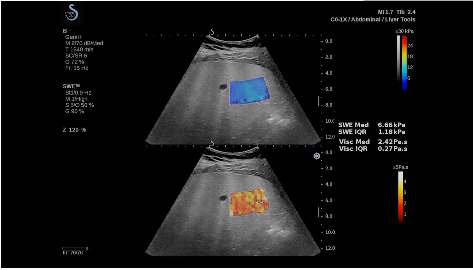

法國聲科影像(SuperSonic Imagine,SSI. Euroniex:FR0010526814)近日發(fā)表公告,宣布其研發(fā)的新一代“極速”超聲成像平臺(UltraFast Imaging),首次實(shí)現了肝臟的多項超聲定量評估新指標同步檢測,包括:Att PLUS,SSp PLUS和Vi PLUS等,基本涵蓋肝臟相關(guān)病理變化指征的如纖維化、脂肪變、炎癥等。據悉,此多項新技術(shù)新將搭載于新Aixplorer系列E超系統。

法國聲科影像公司(SuperSonic Imagine. SA,France),2005年由三位諾貝爾獎級科學(xué)家主導創(chuàng )立,專(zhuān)注于E超的開(kāi)發(fā)和生產(chǎn),是目前世界上唯一可以同時(shí)應用兩種波進(jìn)行人體檢測的系統:縱波形成高質(zhì)量的二維組織結構圖像,而橫波可以使醫生實(shí)時(shí)準確地看到并分析組織的硬度,有效減少有創(chuàng )檢查、避免損傷。

E超是在原有B超、彩超(彩色多普勒CDFI)基礎上研發(fā)成功的新一代超聲剪切波彈性成像系統,是一種能夠全面應用于表淺組織、腹部臟器,血管等方面的組織彈性成像技術(shù)。根據組織硬度彈性值的不同,有效鑒別實(shí)性腫瘤的良惡性。對于惡性病變的診斷具有較高的特異性和敏感性,尤其對于甲狀腺、乳腺、前列腺等小器官,能夠完成常規超聲不能完成的組織定量分析,可以實(shí)時(shí)、全幅、全定量獲得組織彈性(硬度)信息,為鑒別腫瘤的良惡性提供客觀(guān)、量化的診斷依據。